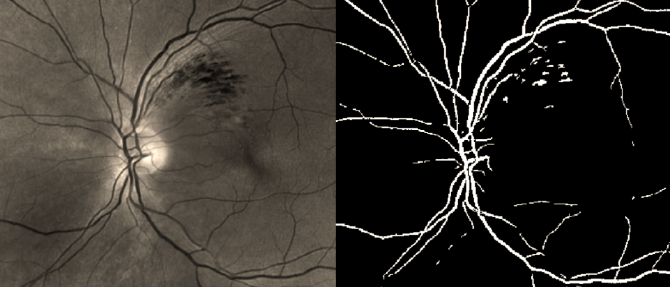

The light sensitive portion (the retina) requires large amounts of nutrient to accommodate metabolic demand, and as such requires two dedicated vascular systems. These systems are both fed from outside the eye, and form an interesting point of coupling between the eye and the external environment. Mathematical modelling of these vasculatures is possible using sophisticated image extraction technique to form an interconnected vascular network. Analysis of these models has been used to quantify fluid pressure changes within the eye, particularly in the aftermath of a traumatic brain injury.